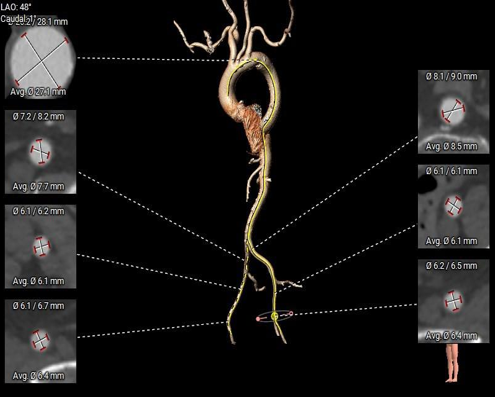

宋光远教授 首都医科大学附属北京安贞医院(点击查看专家详细简历) 技术革新不止,创新求索不辍:一切从患者出发,不断追求创新是内心的坚定。当年‘ALL IN ONE’的探索,正是怀揣着这份初心 —— 通过整合器械与操作,将入路创伤缩至最小,让患者在微创中更快康复,这是技术对患者的温柔承诺。而术中脑保护,是我们为安全筑牢的另一道防线。 此次预装干瓣的临床应用,让我们直面瓣膜“耐久性“临床困境,期待创新技术助力全生命周期管理! 病例概览 患者病史 患者因 “劳力性呼吸困难半年余,加重 20 天” 入院。高血压病史 20 年,最高血压 160/110mmHg;高脂血症病史;反流性食管炎。 超声提示:主动脉流速 Vmax 4.66 m/s,平均压差 53mmHg,左室射血分数(LVEF)40%; 超声诊断:主动脉瓣狭窄(重度)、主动脉瓣反流(轻中度)、二尖瓣狭窄(轻度)、二尖瓣反流(轻度)、三尖瓣反流(轻中度)、左房增大,左室肥厚。 术前CT 瓣环(Annulus)直径:22.9mm,左室流出道(LVOT)直径:周长径 23.8mm;总钙化负荷1239mm³(HU850),钙化集中于无冠窦,且蔓延至 LVOT,呈重度钙化表现;LVOT-Annulus 呈微直筒型,瓣上限制较重。左冠脉开口高度略低,瓣叶不长、窦部空间较大,结合钙化分部情况,预估双侧冠脉遮挡风险较低。室间隔膜部较短(2.4mm)有一定PPI风险,心室大小可,心脏角度64°,升主长度短于胶囊腔长度,同轴有一定困难。 · 造影角度及入路情况:主动脉弓角度可,但降主动脉折曲明显,双侧髂股动脉存在粥样硬化。 手术策略 采用 “极简式” 手术方案:18/20mm 球囊预扩张,植入金仕生物 Prostyle-A 预装干瓣(AV 26),配合长鞘,同时植入脑保护装置以降低卒中风险。 手术过程 球囊预扩:18号球囊预扩 输送系统顺利过弓跨瓣: 瓣膜植入:工作位观察位置适宜,完成植入。 术后即刻:术后造影显示瓣膜位置佳 入路与血管:撤出大鞘后检查,降主动脉仍存在较大弯折;入路闭合良好,无明显出血或血管并发症。 Prostyle A®预装干瓣——助力临床最优化解决方案: √ Mircro-EX™专利抗钙化技术:极简式预装干瓣,不使用戊二醛浸泡,减少钙化成因,干态存储的瓣膜术中无需清洗瓣膜,减少组装步骤,缩短手术时间,尤其适合复杂病例中的高效操作; √ 平衡的径向支撑力:重度钙化的患者,形态展开良好,在横位心等复杂情况下实现稳定锚定及释放; 专家简介 苑飞 首都医科大学附属北京安贞医院(点击查看专家详细简历) 姚晶 首都医科大学附属北京安贞医院(点击查看专家详细简历) · END ·